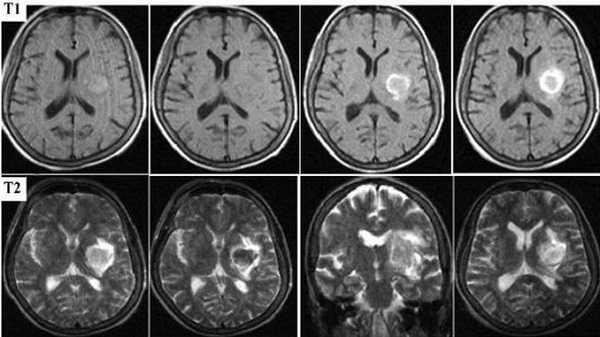

Картина развития ишемического инсульта на МРТ (Т1- и Т2-взвешенные изображения)

Острый период (1-7 день) характеризуется появлением четко ограниченных светлых участков на МРТ в Т2-взвешенном режиме. На Т1 ВИ очаги некроза имеют гипоинтенсивный сигнал.

Головной мозг на МРТ при разных режимах сканирования

Ишемический инсульт

Для заболевания характерно появление очагов некроза, вызванного нарушением кровоснабжения определенного участка мозга. В острой стадии наблюдается утолщение извилин коры головного мозга, стирается граница между серым и белым веществом. В период восстановления зону инфаркта определяют как участок кистозного или глиозного перерождения.

Для лакунарного инсульта, представляющего разновидность ишемии, характерно появление небольших (до 20 мм) очагов и кровоизлияний в области глубинных структур головного мозга. Причиной служит тромбоз мелкой внутричерепной артерии, вызвавший образование кисты (лакуны).